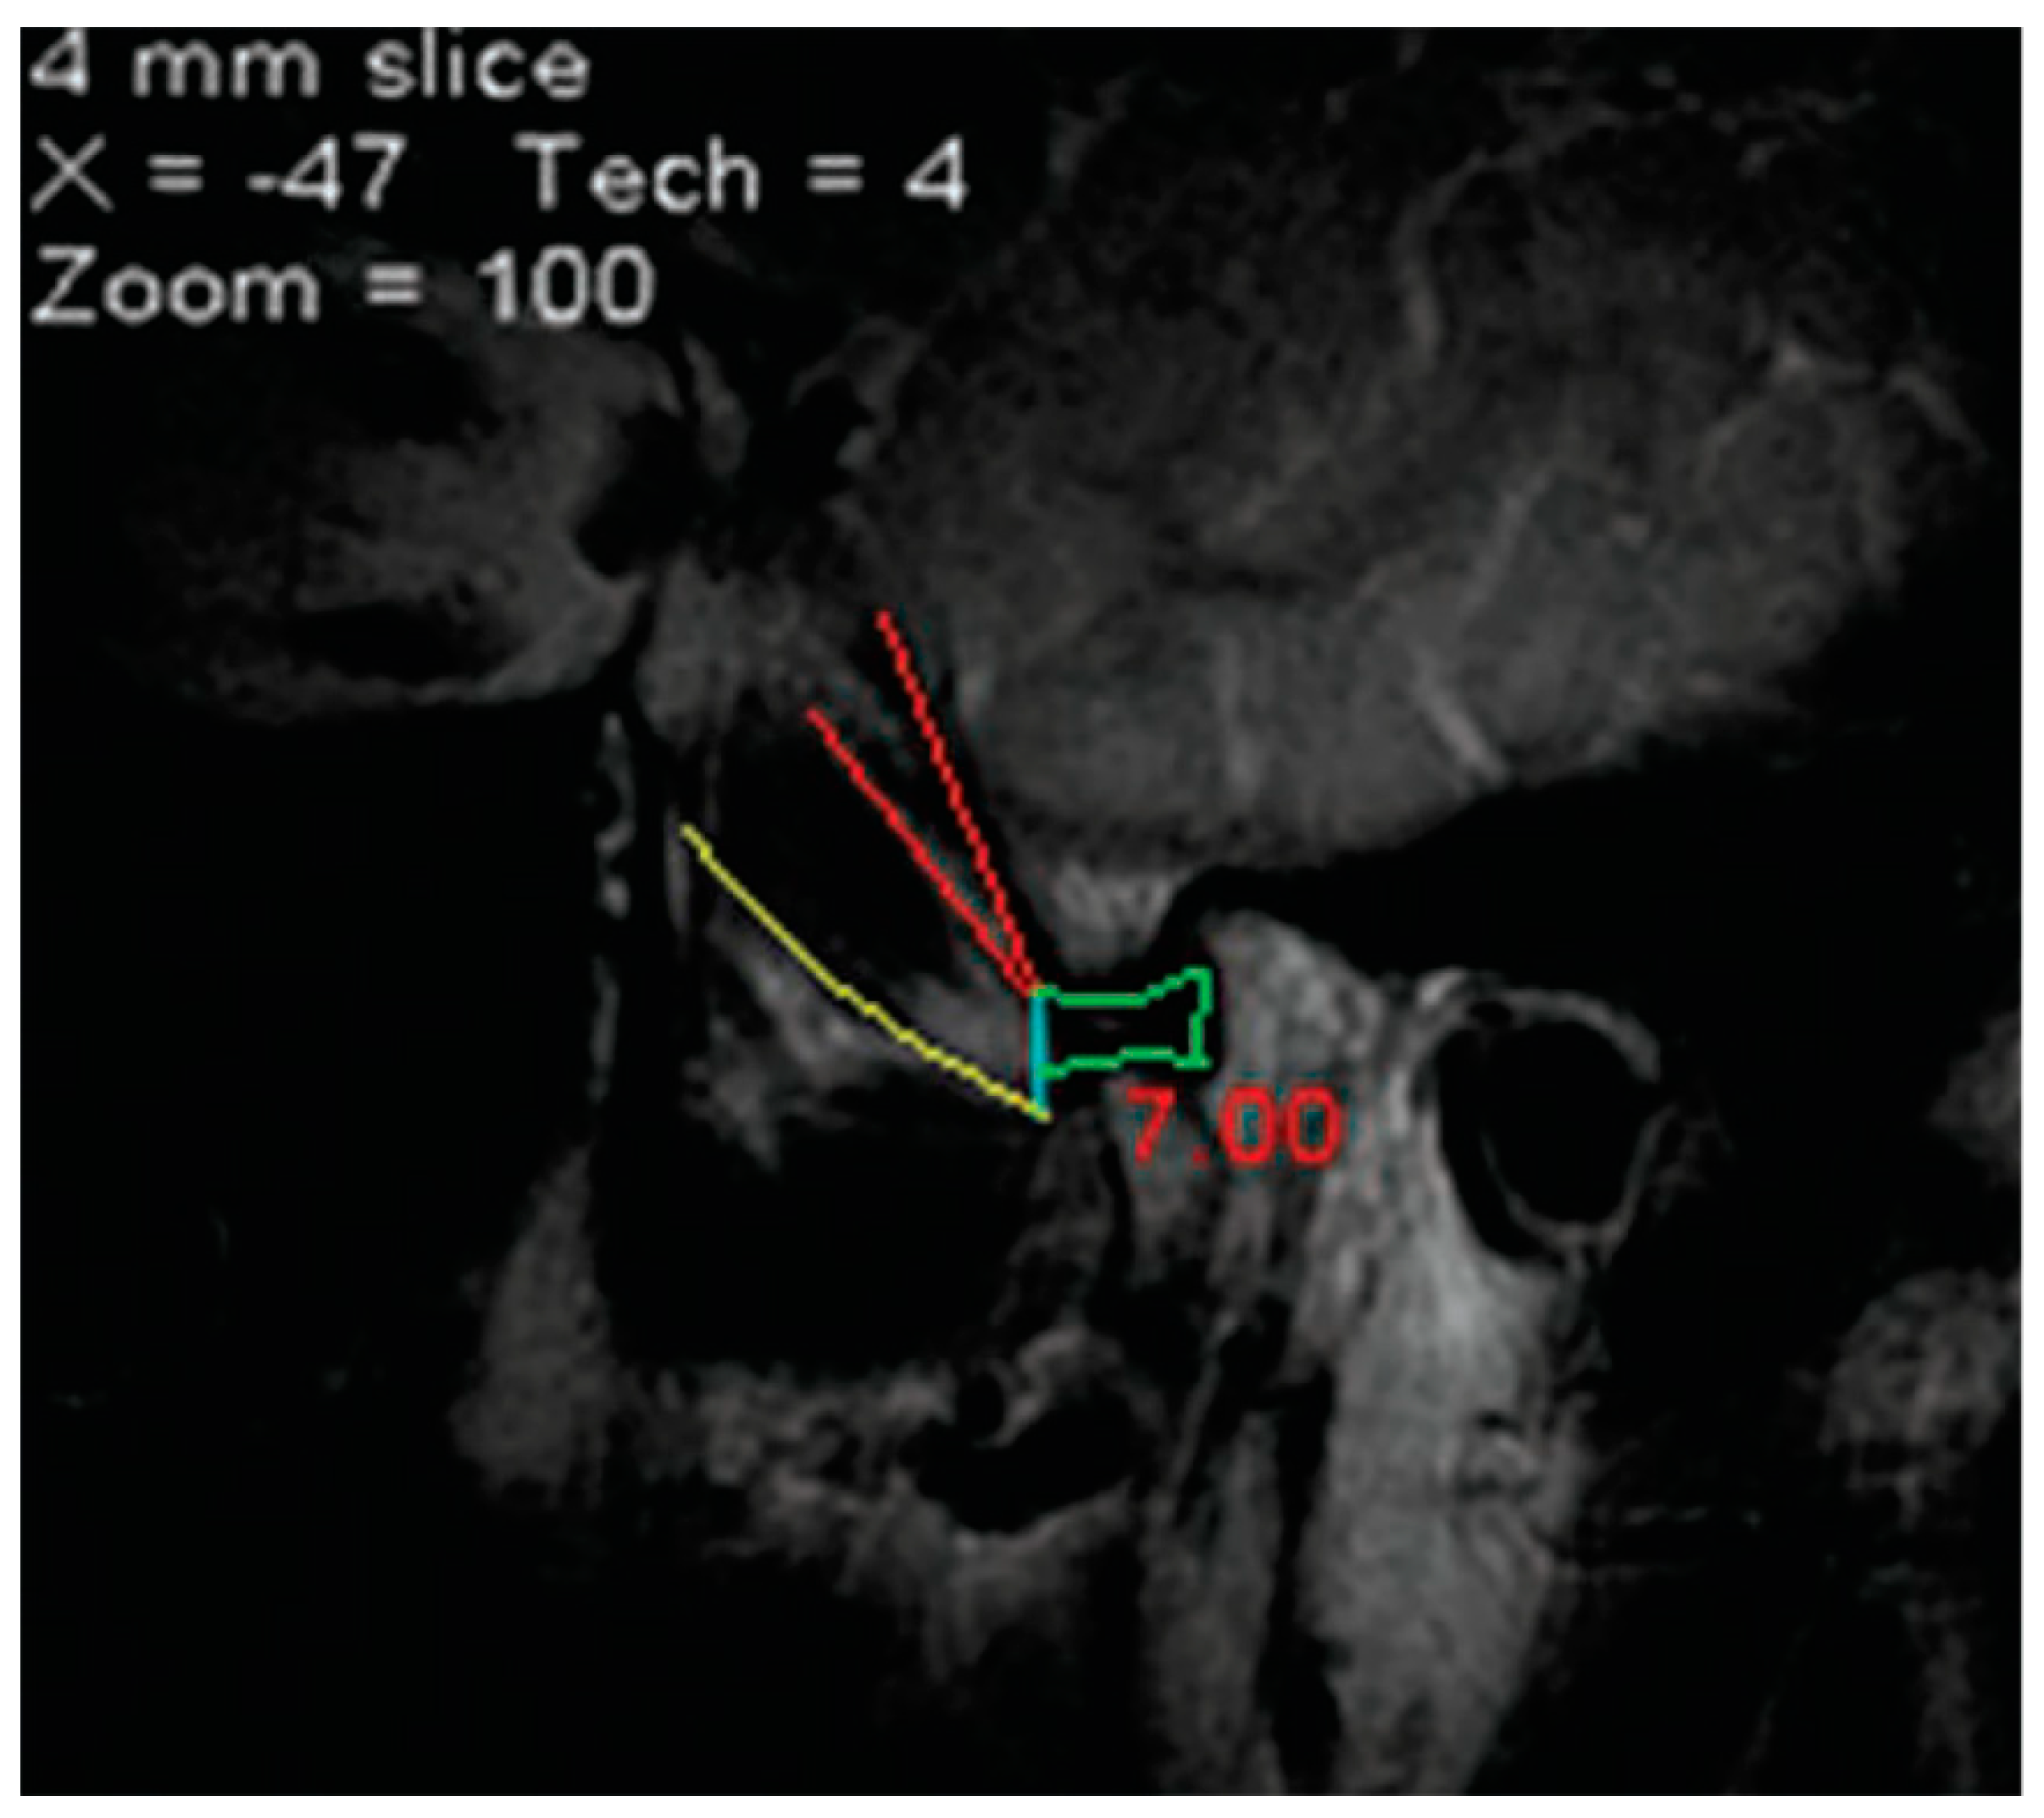

- Rusu, M.C.; Dinca, D. Accessory pterygoid fovea of the human mandibular condyle. Cranio 2021, 39, 452–456. [Google Scholar] [CrossRef] [PubMed]